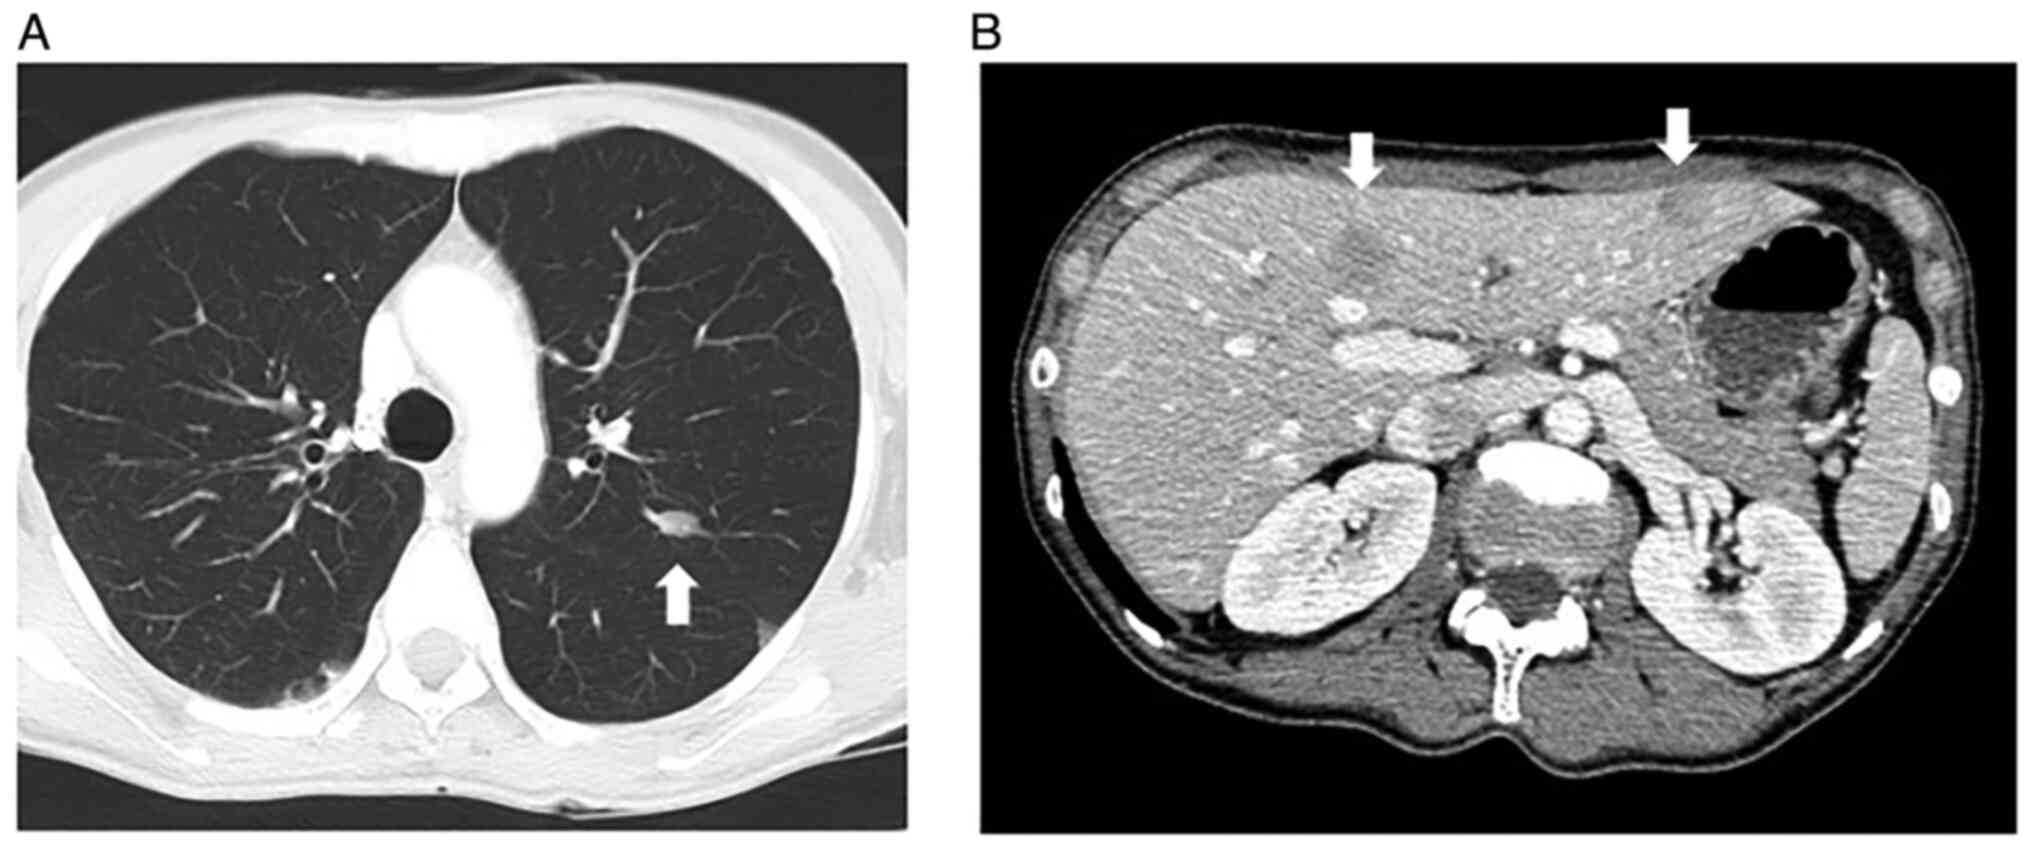

After the operation, she received four courses of adjuvant chemotherapy consisting of ifosfamide (2 g/m2 per day, infusions performed on days 1-5) and doxorubicin (30 mg/m2 per day, infusions performed on days 1-2) every 28-day cycle. However, several subcutaneous metastatic nodules occurred in May 2016. In September 2016, a total of five subcutaneous lesions were resected, two from the anterior chest, and one from the right shoulder, left upper arm, and left lumbar region (Sample 2). All of the lesions were metastatic leiomyosarcomas. In November 2016, multiple metastases were detected in her lung (Fig. 2A) and liver (Fig. 2B) via computed tomography. The first-line systemic chemotherapy, consisting of gemcitabine (900 mg/m2/day; infusions performed on day 1 and 8) and docetaxel (70 mg/m2; infusions performed on day 8) every 28-day cycle, was started, but it was discontinued after two cycles due to the suspected pneumonitis caused by these anticancer drugs. The second-line chemotherapy consisting of eribulin mesylate (1.4 mg/m2/day; infusions performed on day 1 and 8 of every 21-day cycle) was started, but it was discontinued during the second cycle due to progressive disease. The third-line therapy consisting of pazopanib, 600 mg/day orally, was started in April 2017 but was discontinued due to high fever, thrombocytopenia, and punctate erythema throughout the body. At that time, a skin biopsy was performed on her left lower leg (Sample 3), but no metastases of leiomyosarcoma were found. The fourth line of chemotherapy, trabectedin (1.2 mg/m2), was started, but after 2 cycles, there was evidence of progressive disease. A reduced dose of pazopanib, 200-400 mg/day, was re-introduced, and it was continued for approximately 2 years. However, her leiomyosarcoma gradually increased, and she died in January 2020.

Figure 2

CT scan of the (A) lung and (B) liver at the time of metastasis. The metastatic lesions are indicated by white arrows.